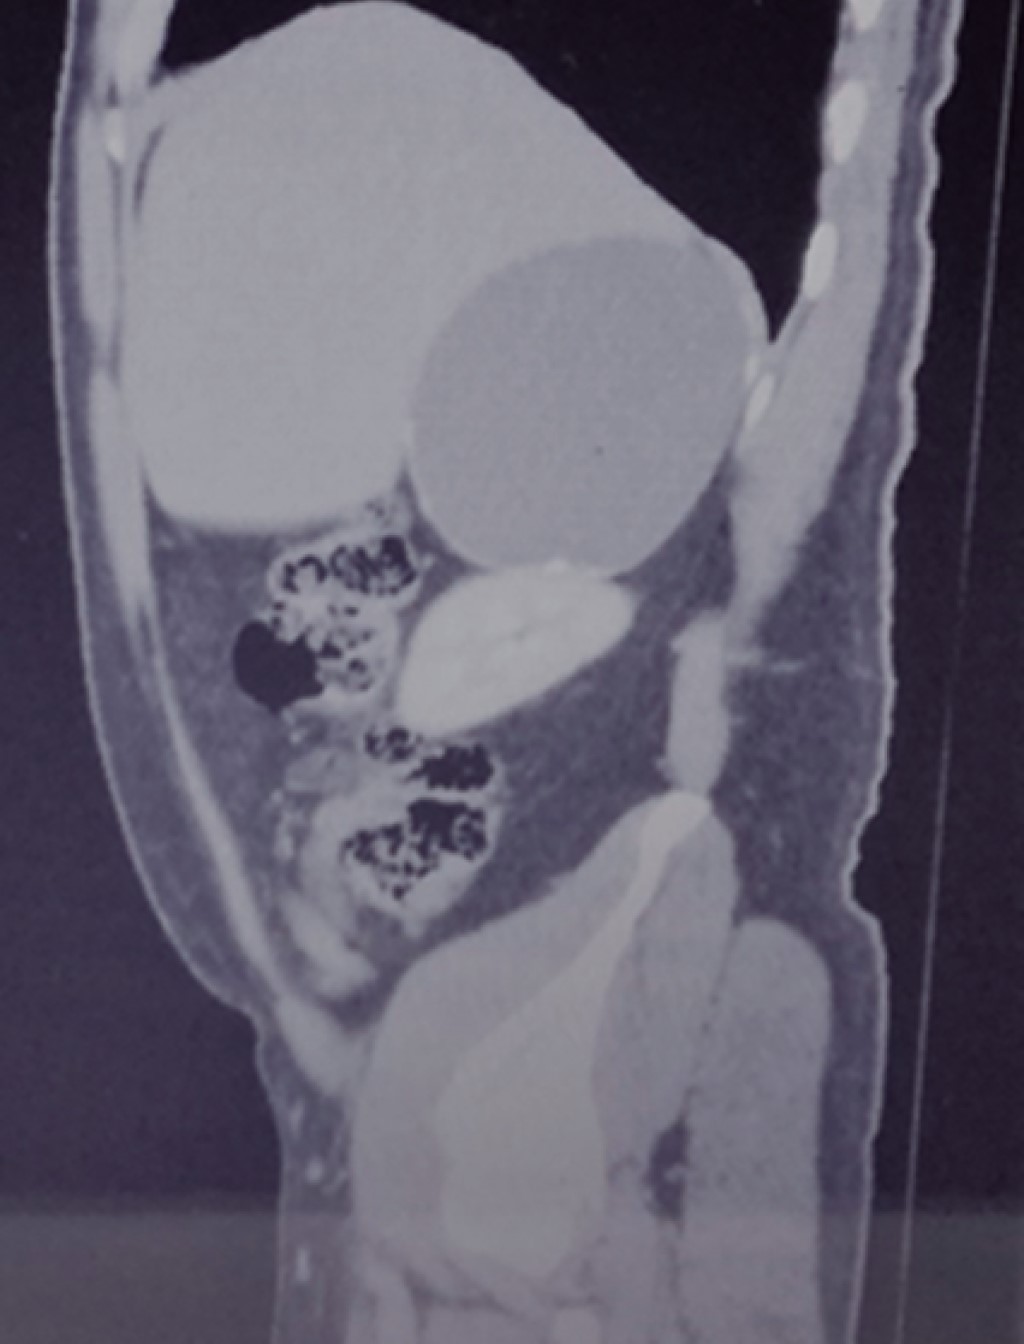

An ultrasound scan done in March reports liver of normal size, shape, and situation with an irregular lower right border, of heterogeneous echogenicity due to the presence of a rounded shape anechoic mass with well-delimited borders and thin walls suggestive of a simple cyst (Figures 1 and 2).

In May 2018 he had normal cytology blood cell counts, liver and renal function tests, and coagulation parameters. No cortisol, aldosterone, urinary catecholamine or metanephrine measurements were done. An abdominal CT scan performed in May reports a right adrenal gland hypodense image with a maximum diameter of 101 mm with calcification images inside it that was exerting occupational and compressive effect on surrounding structures (Figures 3, 4, 5 and 6). Once internal medicine service completed his preoperative assessment, an open anterior surgical approach was scheduled. He was given antibiotic prophylaxis with ceftriaxone 2 g in a single dose before a right subcostal incision was made and we proceeded to electrocautery removal of the right adrenal cyst of 10 × 9 cm. Adhesions to the liver were found and a content of approximately 400 ml of hyaline fluid and calcifications of about 20 × 40 mm in its interior were seen. A Penrose drainage of ½" (19 mm) was placed in the subphrenic space due to the suspicion of postoperative hemorrhage.

Histopathological report was of an adrenal pseudocyst associated with old hemorrhage, fibrosis, and extensive dystrophic calcification. The patient was discharged on the third day of hospitalization with follow-up in the ambulatory setting for four months postoperatively with control with hepatic and right renal ultrasound scans. There were no complications (Figure 7).

Figure 1

Figure 2